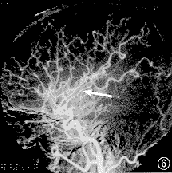

MRI可清晰顯示早期缺血性梗死、腦幹及小腦梗死、靜脈竇血栓形成等,梗死後數小時即出現T1低信號、T2高信號灶,出血性梗死顯示其中混雜T1高信號。釓增強MRI較平掃敏感。功能性MRI彌散加權成像(DWI)可早期診斷缺血性卒中,發病2小時內即顯示缺血病變,為早期治療提供重要信息。DSA可發現血管狹窄及閉塞部位,顯示動脈炎、Moyamoya病、動脈瘤和靜脈畸形等。